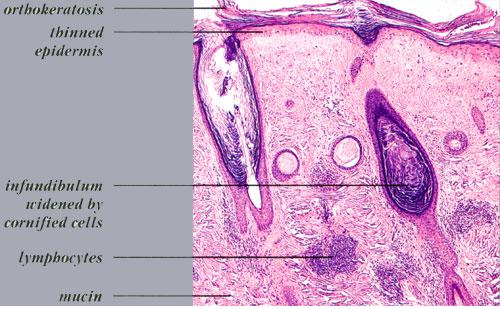

Alopecia of Discoid Lupus Erythematosus = الحاصة بسبب الذئبة الحمامية القرصية